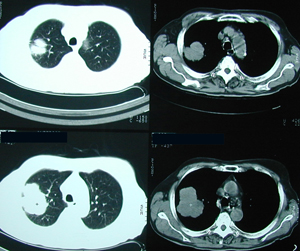

Εικόνα 3

Αξονική τομογραφία θώρακος που δείχνει μάζα εκ μαλακών μορίων ( όγκος ) στον άνω λοβό του δεξιού πνεύμονος.